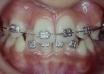

case dot 排整牙齒